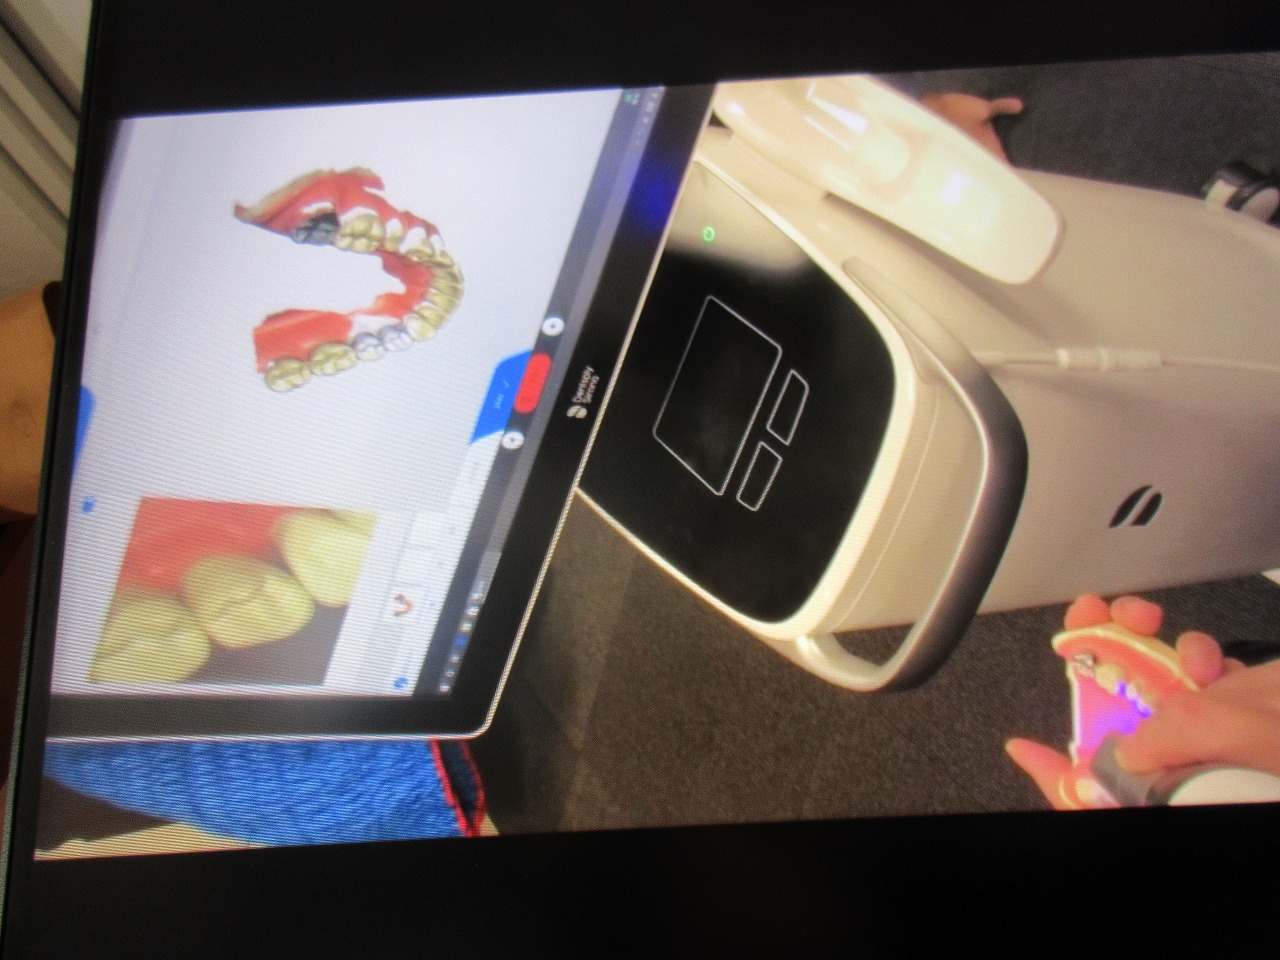

臨床例も挙げます 最新鋭のセレックプライムスキャンがこころ歯科にやってまいりました これによりセラミック治療をはじめマウスピース矯正、総入れ歯の印象まで多くの症例が型取りを行わずにできてきます|お知らせ |広島市安佐南区の歯科医院

臨床例も挙げます 最新鋭のセレックプライムスキャンがこころ歯科にやってまいりました これによりセラミック治療をはじめマウスピース矯正、総入れ歯の印象まで多くの症例が型取りを行わずにできてきます

臨床例も挙げます 最新鋭のセレックプライムスキャンがこころ歯科にやってまいりました これによりセラミック治療をはじめマウスピース矯正、総入れ歯の印象まで多くの症例が型取りを行わずにできてきます

破折症例もこのようにプライムスキャンにてセラミックにて修復しています